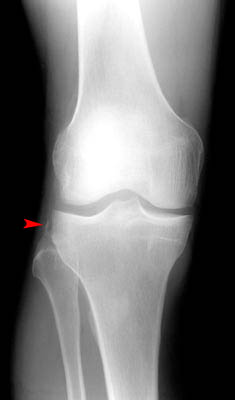

• Avulsion of the lateral tibia at the attachment of the lateral capsule.

• Varus stress and internal rotation of the leg that occur when the knee is flexed place excess tension on the lateral capsule and associated ligaments. Too much stress can result in avulsion.

• Due to the mechanism of injury, anterior cruciate ligament tears are commonly associated with this type of fracture.

AP view